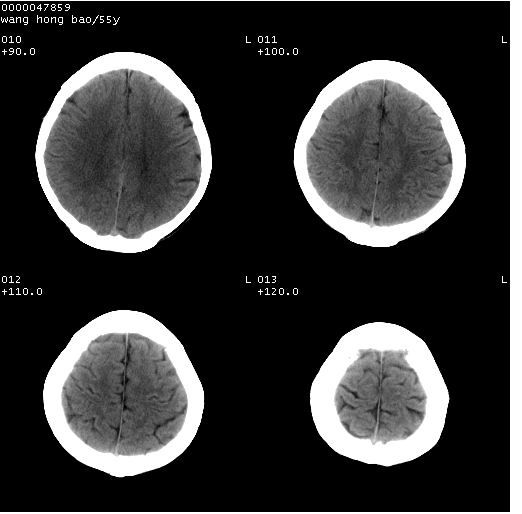

以下是引用dyqct在2008-5-3 23:36:00的发言:[br]桥前池区可疑蛛网膜囊肿。其它未见明显异常。建议做mri。

以下是引用qiushi在2008-5-4 10:10:00的发言:[br]鞍上池前缘突出影为双侧额叶直回;箭头所指为双侧正常之人字缝.[br]桥前池区可疑表皮样囊肿或蛛网膜囊肿,必要时mri

以下是引用zjzjr在2008-5-4 14:50:00的发言:[br]桥前池区可疑蛛网膜囊肿。其它未见明显异常。建议做mri。